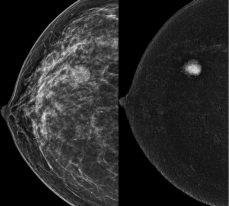

108 Harley Street introduces London's first private HOLOGIC Contrast Enhanced Mammography System, revolutionising breast cancer screening. Mammography has long been the primary method for detecting breast cancer at an early, treatable stage However, with the advent of Contrast Enhanced Mammography (CEM), a specialised and advanced mammography test, breast imaging has reached new levels of precision and detail Our facility now offers this state-of-the-art technology, ensuring patients receive the highest quality breast cancer screening available

CEM goes beyond the capabilities of standard mammography by utilising a special dye (contrast) injected into the patient's arm, enhancing the visibility of breast tissue changes.

CEM is recommended for several patient groups, including those who require assistance in resolving findings detected through conventional breast imaging, individuals needing pre-operative staging of breast cancer, patients with contraindications or intolerance to MRI (e g , pacemakers or claustrophobia), and patients over 40 who have suspected cancer based on ultrasound but normal mammography results Additionally, CEM can be employed as an alternative to MRI for women at an increased risk of developing breast cancer, such as those with dense breasts or a strong family history.

To learn more about CEM or refer a CEM patient please contact our X-Ray